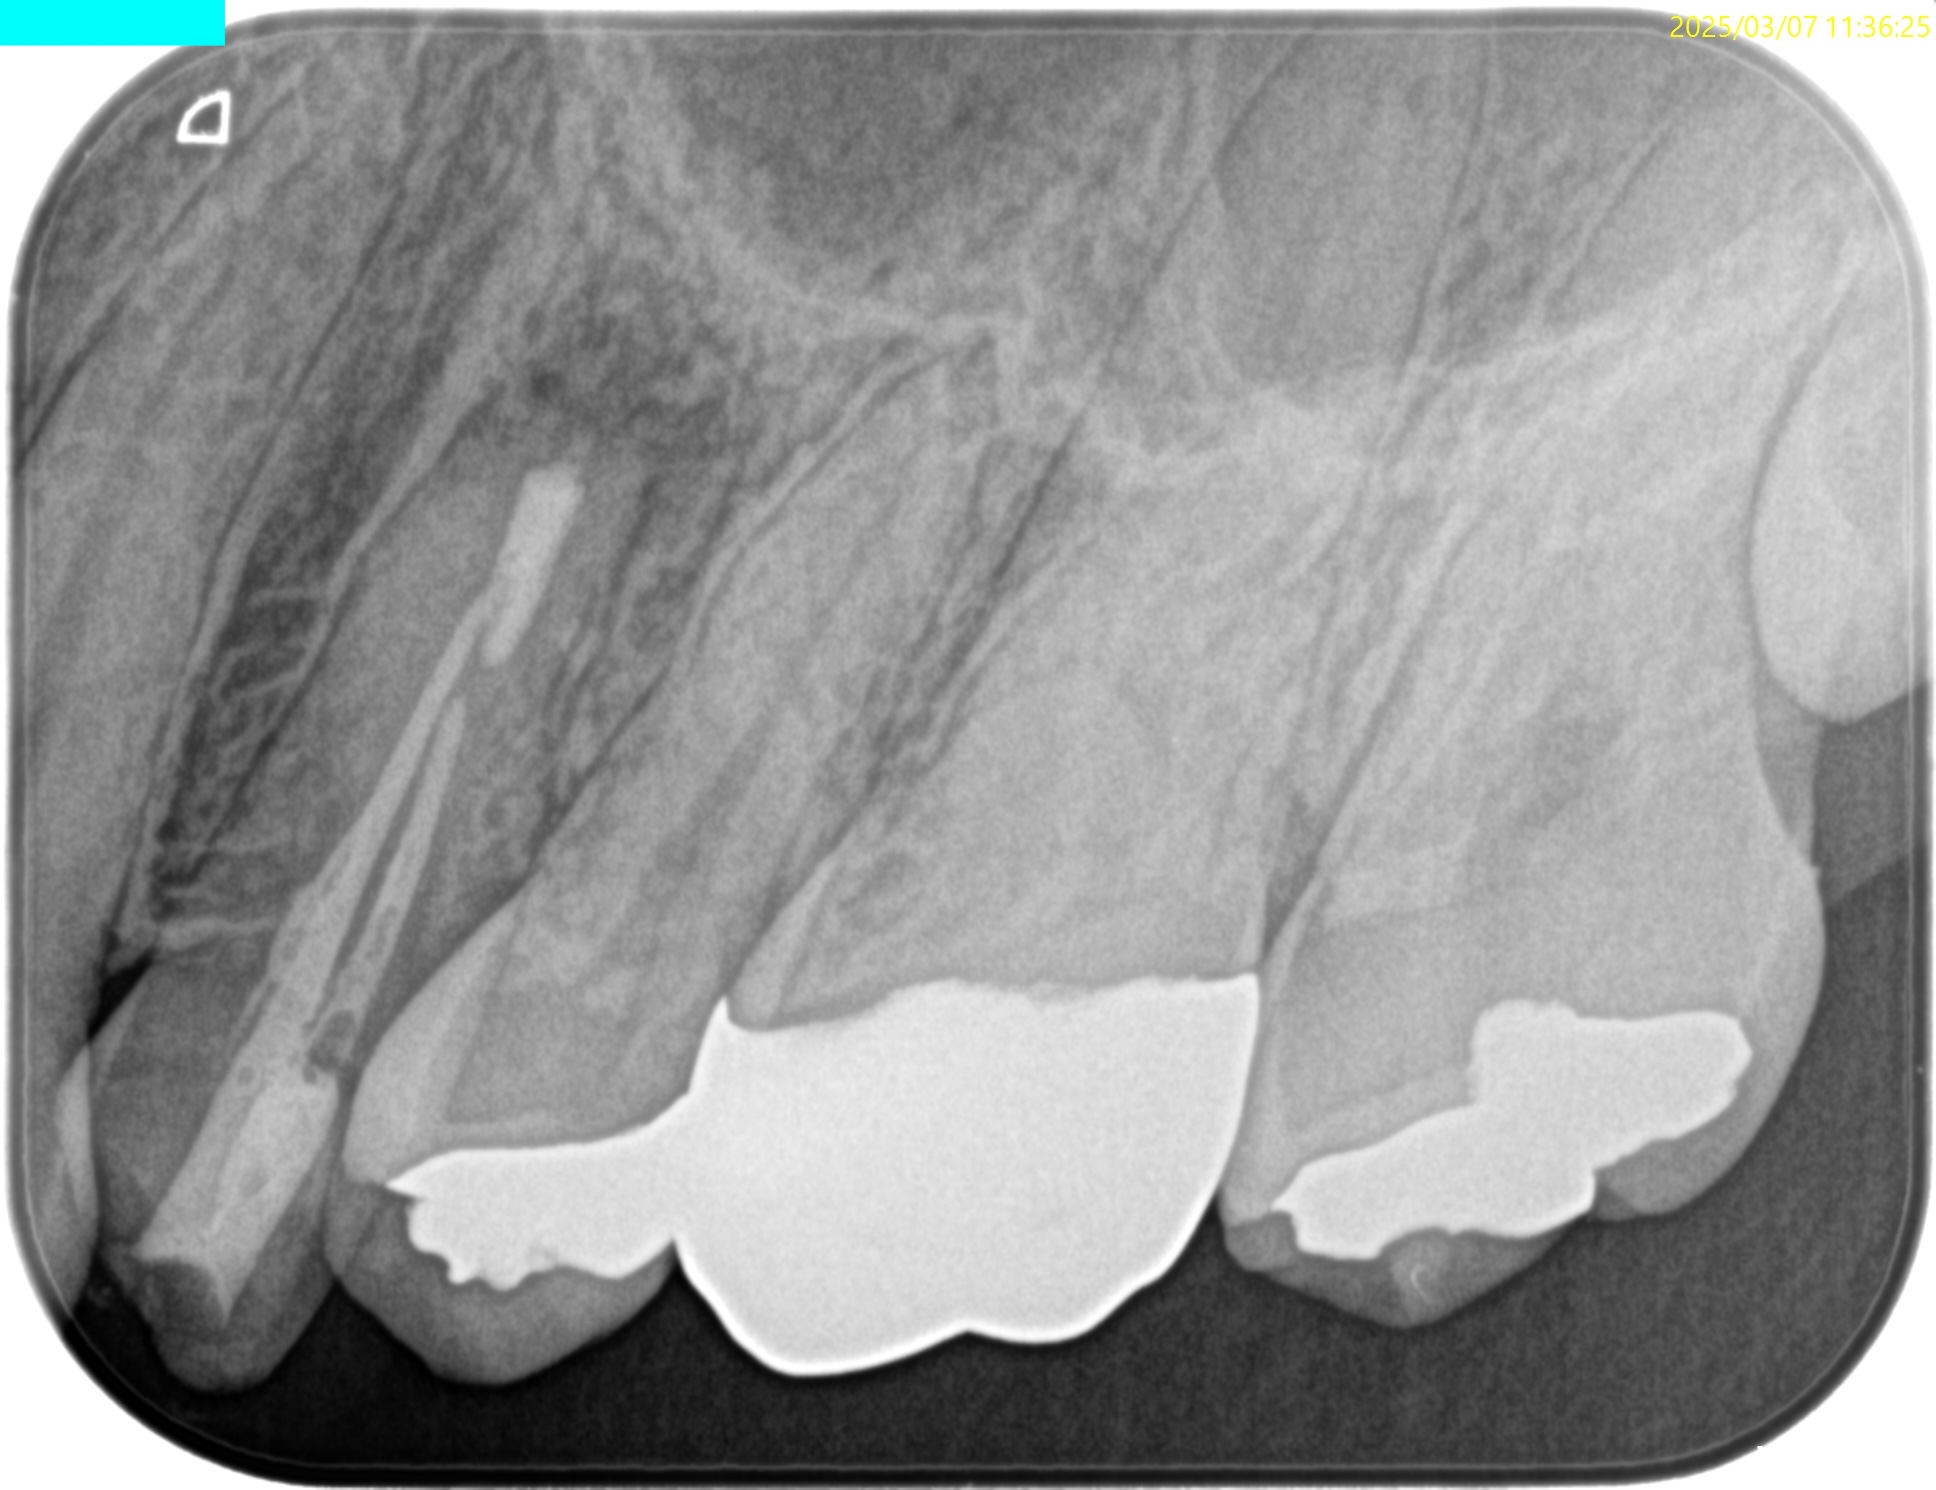

#12 Apicoectomy 1yr recall(2026.2.27)

1年前と比較した。

問題は解決した。

ということでこの日で終診となった。

長い間、お疲れ様でした。